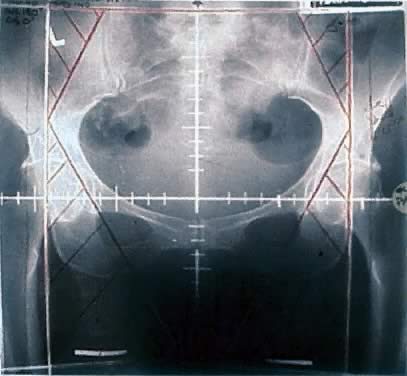

Vulvar tumors require treatment of the primary site as well as draining lymph nodes. Areas at risk for harboring microscopic disease typically receive doses between 45 and 50 Gy, whereas gross disease usually requires doses above 60 Gy. Opposed anteroposterior (AP/PA) treatment fields encompass the pelvic lymph nodes, inguinofemoral lymph nodes and perineum. High-energy beams (10 mV or more) delivered from opposing sides of the target yield a homogeneous dose distribution across wide treatment depths. This characteristic is important because the target volume often lies across several centimeters of tissue, different targets lie at different depths, that is, the groin versus the pelvic lymph nodes, and because the body has a heterogeneous surface. Simulation films used for the treatment of a typical vulvar cancer patient are shown in Figures 3 and 4. The radiation beam can be pictured passing through the plane of the page. The grid marks the central rays of the photon beam and the straight lines at the corners represent the area in the beam's path, which is blocked by Cerrobend, a metal that is liquefied when heated, poured and then allowed to cool in the shape of the area of desired protection. Thus, 1-cm Cerrobend attenuates the radiation beam by 50%. Five to six centimeters of block are required to diminish the radiation dose to less than 5% at the surface of the skin. In the example shown, bowel and soft tissue that are not overlying or underlying targets of interest are blocked out. One structure of concern for radiation damage is the head of the femur. The posterior treatment field shown in Figure 4 does not pass through the femoral heads and therefore excludes the groin, which would be underdosed without a make-up dose from the anterior side. Because the inguinal lymph nodes lie close to the skin surface, treatment of this area with separate electron beams, which deposit more energy near the skin surface compared with photons, allows coverage of the groin while limiting the total dose to the femoral heads. After 45 to 50 Gy is delivered to areas at risk for microscopic disease, the treatment field is reduced to cover only that area of gross tumor that can be marked at the time of initial simulation with a radiopaque wire. Treatment can then proceed to the necessary dose.

Fig. 3. Anteroposterior portal including primary site, pelvic nodes, and groins. Electron fields are shown in purple. This area receives dose contribution from both photons and electrons.

Fig. 4. Posterior simulation film for patient with vulvar cancer. Note that the femoral heads are blocked.

A different technique to cover the groin without overdosing the femoral heads involves the use of only photon fields. The anterior and posterior fields are identical to those shown in Figures 3 and 4, but no separate electron fields are used. Instead, a central partial transmission block is placed in the path of the anterior beam such that the primary site and pelvic nodes receive more dose contribution from the posterior field whereas the extended portion of the anterior field that covers the groin is unattenuated. The “wing field” technique has been well described and analyzed by Kalend and colleagues who found that the divergence of the posterior beam creates a 30% hot spot in the groin, which can be greatly reduced by tapering the edges of the anterior transmission block increasing dose contribution to the wing portion of the field from the anterior beam.51